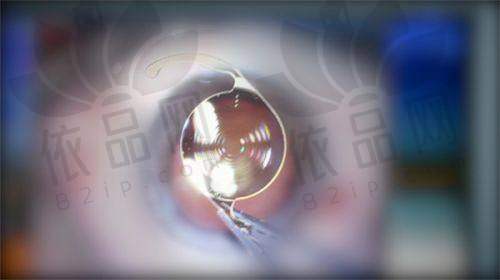

多样化的眼科检查:从基础的视力检查到复杂的眼底病变筛查,爱尔眼科配备了齐全的检查设备,确保诊断正确、治疗有效。